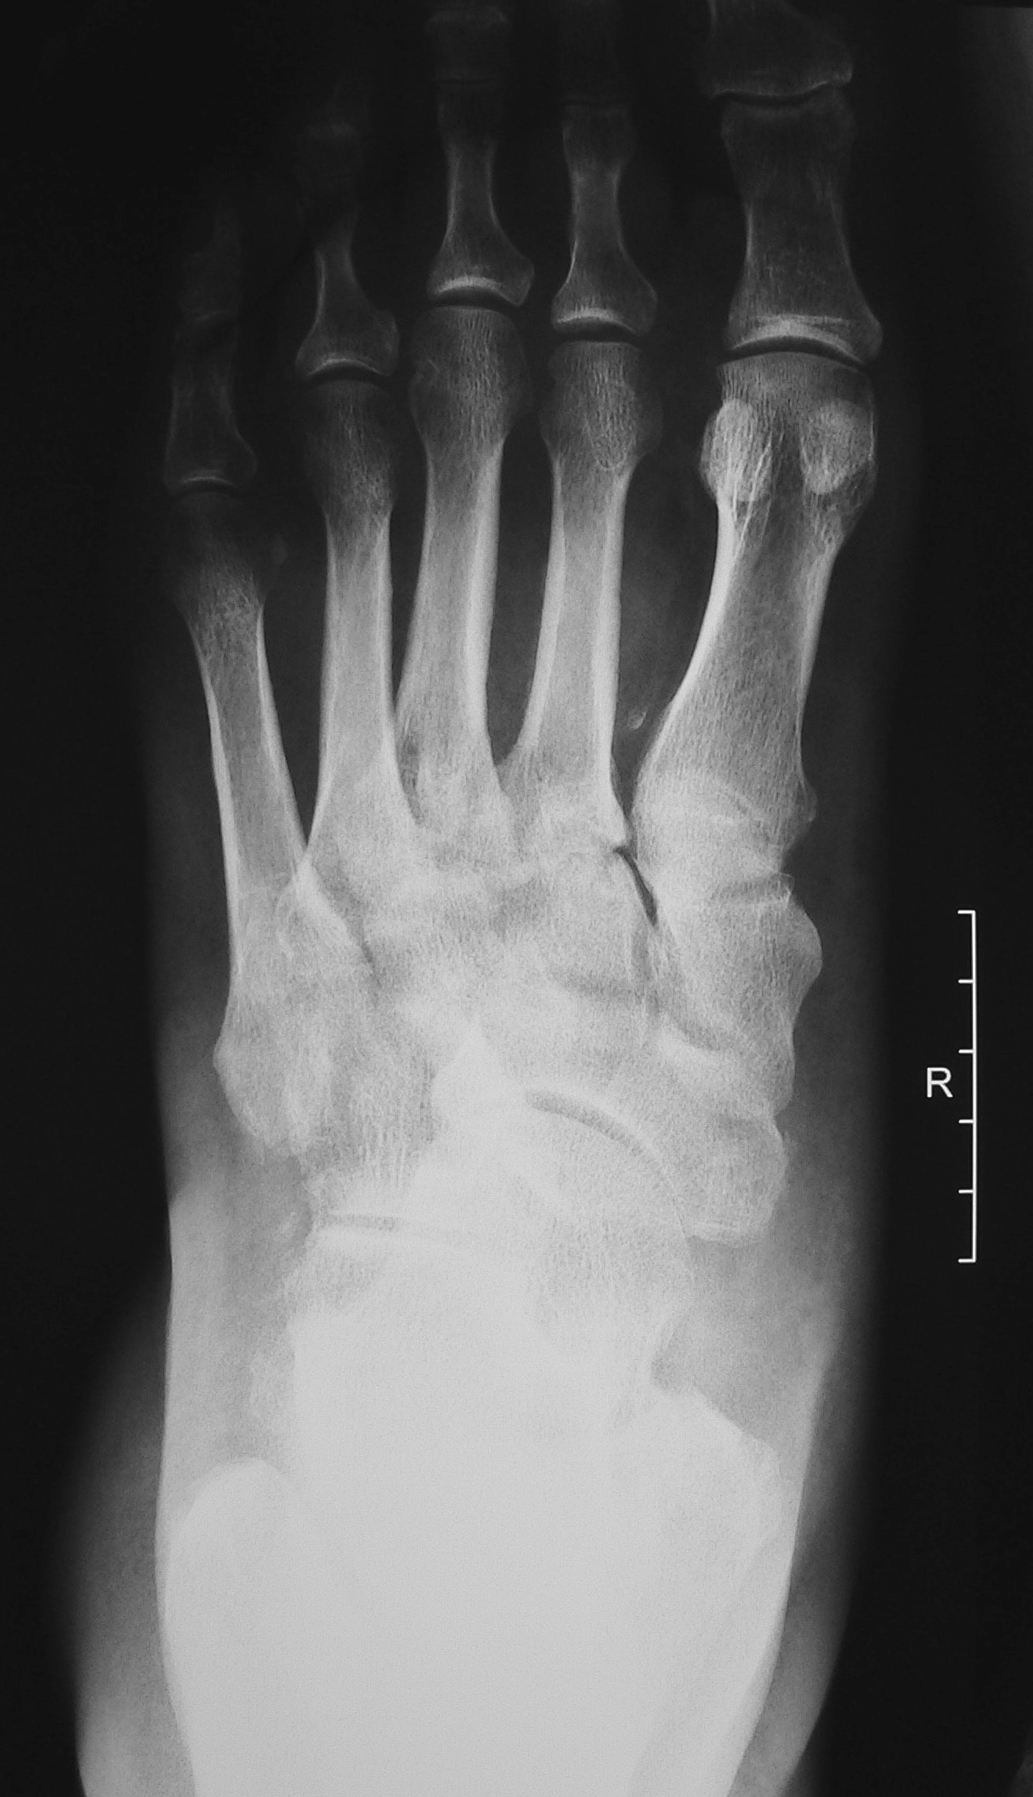

На рентгенограмме (начало октября 2018 г.) отмечается небольшая дислокация ладьевидной кости, нечеткость границ II, III клиновидных костей (возможное их разрушение), а также неизвестной давности экзостоз таранной кости (рис. 5, 6). В связи с неоднозначностью рентгенологических данных выполнена МР-томография. Выявлен отек костного мозга таранной, ладьевидной, кубовидной кости, деструкция клиновидных костей.

Рис. 5. Рентгенограмма стопы больного 2. Прямая проекция.